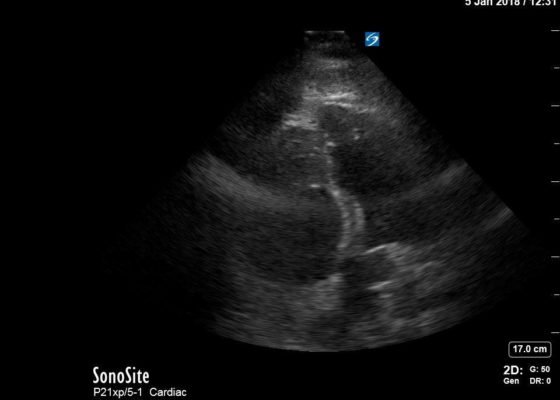

Right Ventricular Dilation in Patient With Submassive Pulmonary Embolism

DOI: https://doi.org/10.21980/J82P84Bedside echocardiography four chamber view revealed enlarged right ventricular (RV) to left ventricular (LV) ratio (greater than 1) on apical four-chamber view (see red and blue outlines respectively). The right atrium is not clearly delineated in this image and therefore is not outlined. One can also rule out a large pericardial effusion as the cause of her dyspnea, since there is no large hypoechoic collection surrounding the heart on either four- chamber view or parasternal long view.